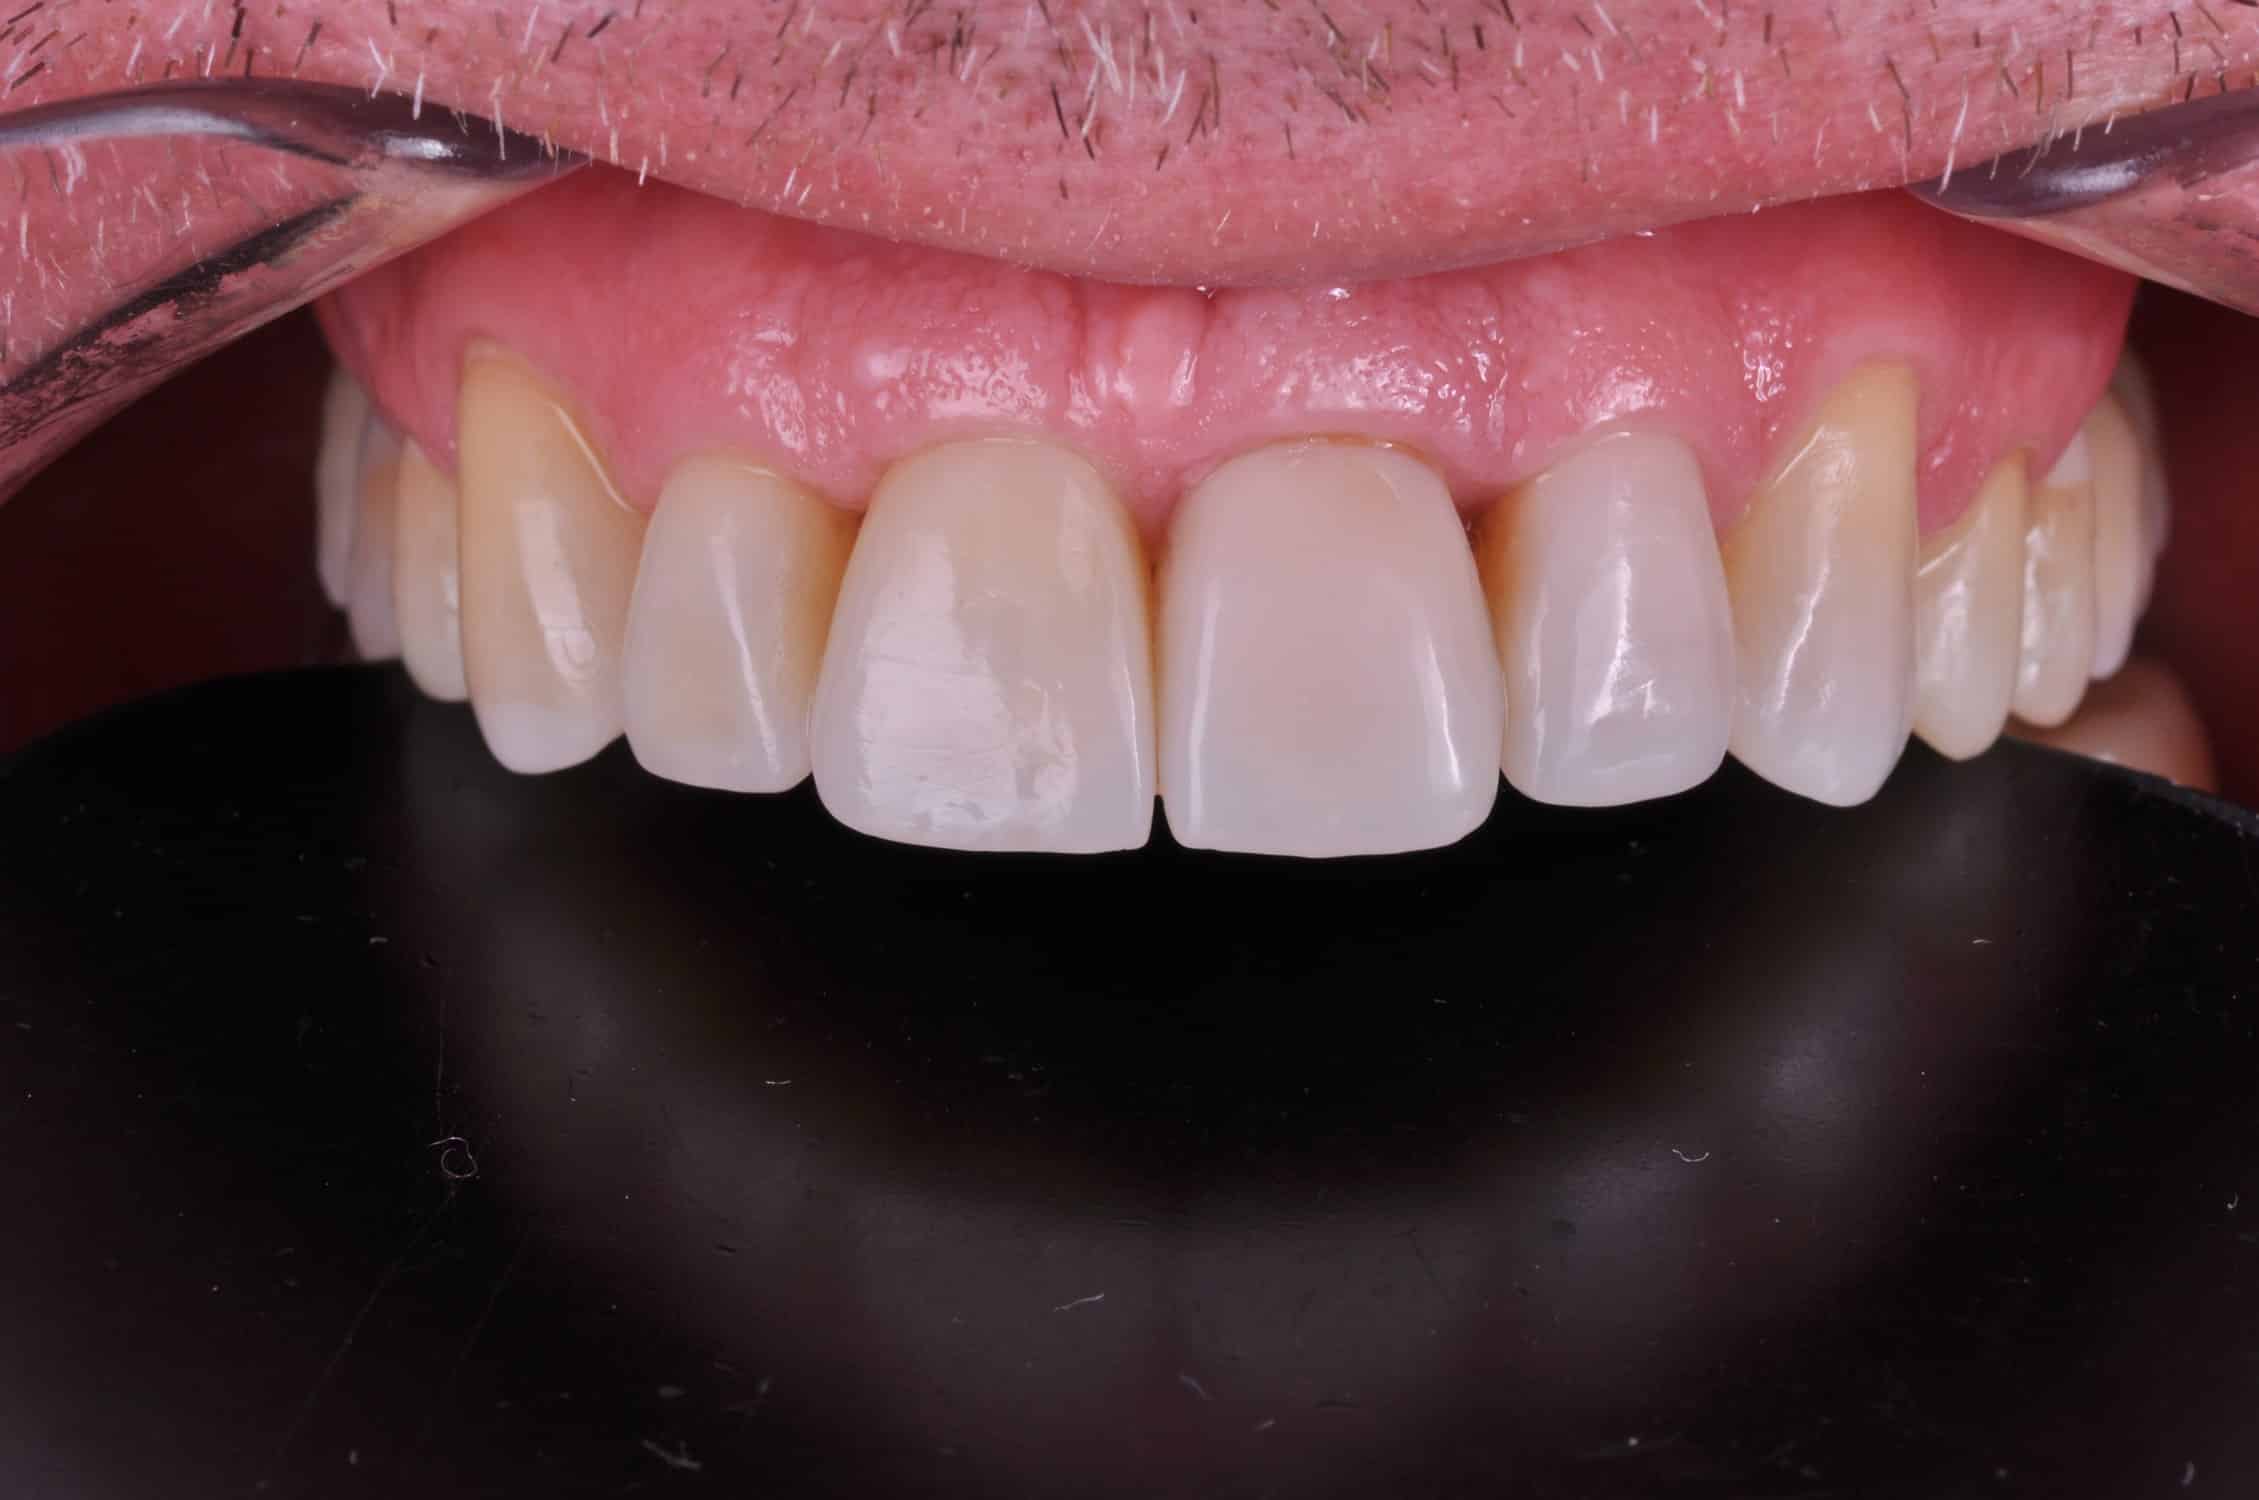

Doar astfel putem crea profilul de emergență corect al coroanei dentare, ceea ce permite conformarea papilei și a sulcusului.